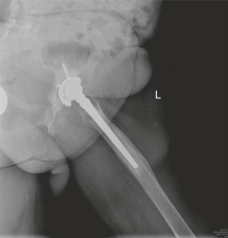

Initial radiographic evaluation consisted of standardized, weight-bearing anteroposterior (AP) and lateral views of the right hip, alongside a full-length AP pelvis radiograph to assess bilateral symmetry, pelvic obliquity, and offset.

The AP Pelvis radiograph demonstrated catastrophic failure of the index arthroplasty. There was evidence of severe, expansile acetabular osteolysis, predominantly localizing to DeLee and Charnley zones 1 (superior) and 2 (medial). The uncemented acetabular shell exhibited significant superior and medial migration, with apparent protrusion of the medial wall into the true pelvis. A continuous, wide radiolucent line (>2 mm) was visible at the bone-prosthesis interface, confirming gross aseptic loosening. The teardrop was obliterated, and the Kohler's line (ilioischial line) appeared compromised, raising the clinical suspicion for an uncontained medial defect or impending pelvic discontinuity.

The lateral radiograph corroborated the AP findings, further delineating the extent of anterior and posterior column involvement. The femoral component also exhibited unequivocal signs of failure. Extensive radiolucency was evident at the bone-prosthesis interface spanning Gruen zones 1, 7, and 2, consistent with proximal osteolysis. Distally, in zones 3, 4, and 5, there was prominent cortical hypertrophy and pedestal formation at the tip of the stem. This radiographic pattern is pathognomonic for proximal stress shielding combined with distal point loading, indicating a loss of proximal fixation and subsequent micro-motion leading to distal toggle. Minor axial subsidence of the femoral stem (approximately 8 mm) was also noted when compared to immediate postoperative radiographs from 15 years prior.

Based on the comprehensive imaging suite, the acetabular defect was classified as a Paprosky Type IIIB. This classification signifies severe superior migration (>3 cm), massive volumetric bone loss, an incompetent superior dome, and a teardrop that is frequently destroyed or significantly altered, yet with the maintenance of pelvic continuity. The femoral defect was classified as a Paprosky Type III, characterized by extensive metadiaphyseal bone loss with intact diaphyseal bone distal to the isthmus, capable of providing initial mechanical stability for a revision stem.